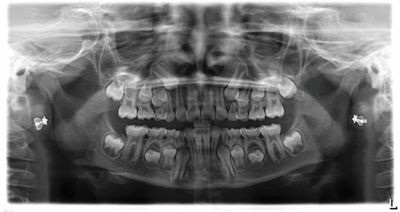

The treating doctor explained that the patient had undergone a rapid palatal expander (RPE) two years earlier for severe crowding and a crossbite (Figs. 4–5). Despite that, the UR3 appeared to be off course. “I’m more of a minimalist every year when it comes to Phase I treatment,” the doctor wrote. “In this case, it looks like a second round of RPE could save the day.”

Fig. 4: Records from two years ago, prior to RPE.

Fig. 5